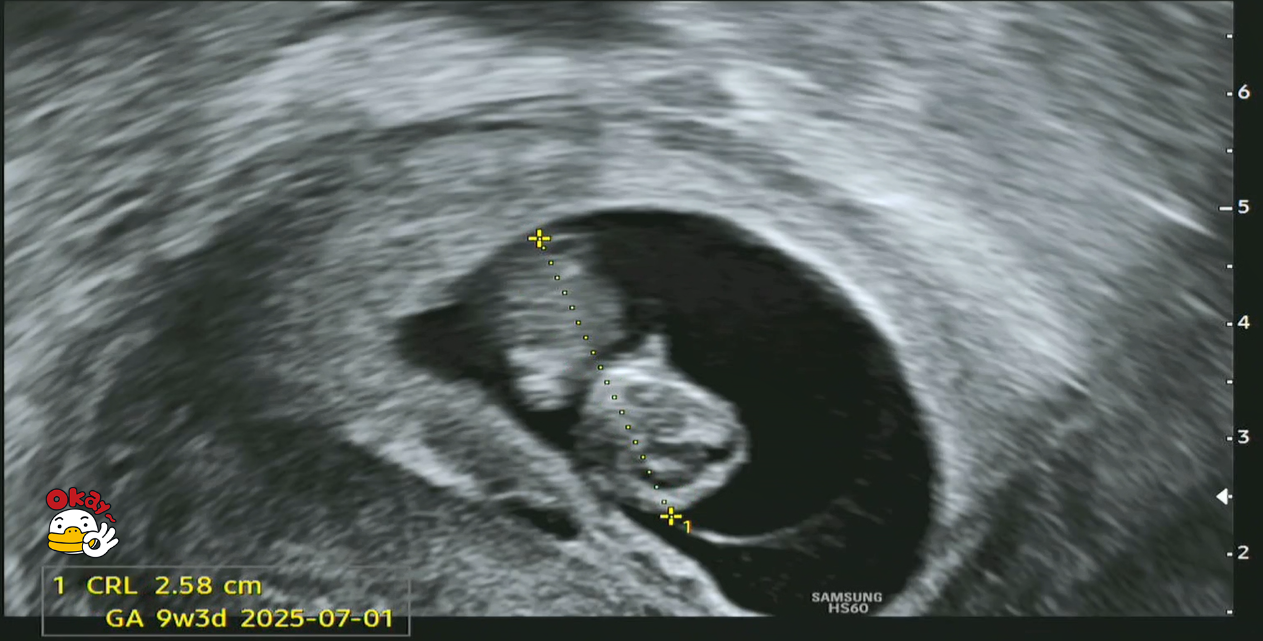

제가 우리 '팡팡이'의 초음파 사진을 분석(?)해보니, 크기는 22.8mm이고 심장 박동수도 186 bpm으로 지극히 정상으로 보입니다.

9주차 태아 크기.png

[왼쪽 - 심장 박동수(186 bpm), 오른쪽 - 태아 크기(22.8mm)]